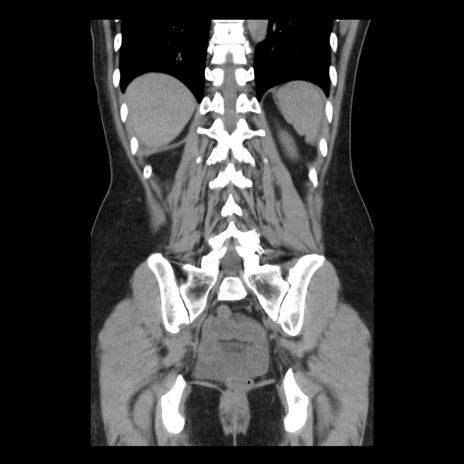

症例10(冠状断像)

【症例】 50歳代女性

【主訴】 腹痛

【現病歴】前日生レバーを食べた。今朝に排便あり。 昼前に突然発症の腹痛を生じ、当院救急外来を受診した。

【既往歴】 子宮筋腫にてで子宮全摘後

【身体所見】 意識清明、腹部:平坦、軟、下腹部やや左を中心に圧痛・反跳痛あり、筋性防御あり

【データ】WBC 7800、CRP 0.07